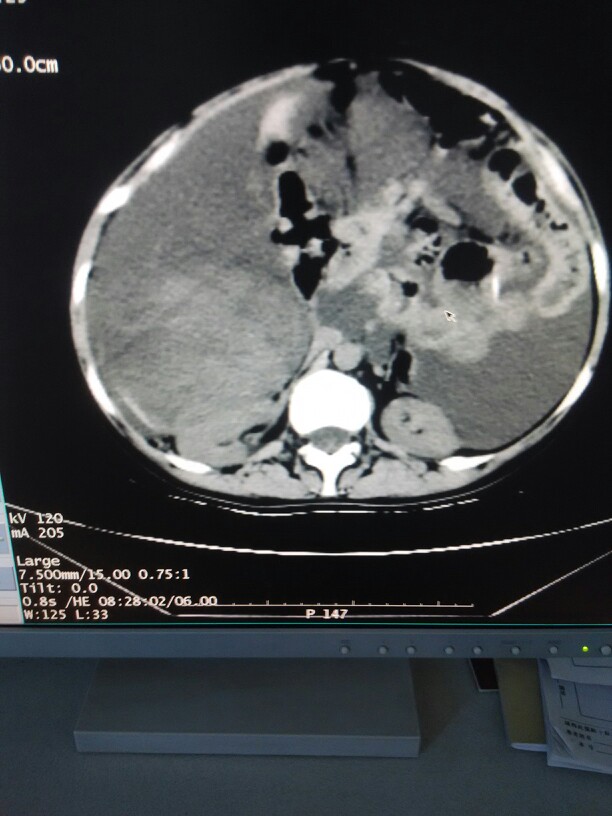

患儿男,9天,因“早产后9天,肝功能异常、血小板减少2天”于2012年6月入院。 病史系怀孕3次生产3次(G3P3),孕36周因“瘢痕子宫”剖宫产,出生体重2135克,羊水Ⅲ度混,阿普加(Apgar)评分正常,脐带、胎盘情况不详。 出生后十余分钟出现气促、发绀伴呻吟,当地医院予持续气道正压通气(CPAP)辅助呼吸、“肺泡表面活性物质”气管内滴注、抗感染等治疗,气促、发绀好转。入院2天前查肝功能“丙氨酸氨基转移酶(ALT)638.8U/L,天冬氨酸氨基转移酶(AST)2990U/L”,血常规“血小板(PLT)42×109/L”,予护肝、补充凝血酶等治疗后,复查血常规示“PLT35×109/L”,为进一步治疗转运入院。 临床表现入院查体体温34.5℃,脉搏120次/分,呼吸48次/分,血压54/36(41)mmHg,体重2010g。反应差,面色苍灰,全身多处可见淤斑,皮肤中度黄染,前囟平软,颈软,呼吸欠规则,双肺呼吸音粗,可及湿音,心律齐,心音中,未闻及杂音,腹软,肝脾肋下未及,四肢肌张力低,肢端凉,原始反射弱。 辅助检查凝血谱:凝血酶原时间(PT)>110s,活化部分凝血活酶时间(APTT)117.6s,凝血酶时间(TT)>110s,纤维蛋白原0.25g/L,D二聚体>2000μg/L。生化:总胆红素(TBil)204.4μmol/L,直接胆红素(DBil)71.8μmol/L,ALT553U/L,AST2181U/L,肌酸磷酸激酶(CKMB)81U/L。血培养含真菌:阴性;脑脊液检查:黄,清晰,潘氏试验(+),白细胞18.0×106/L,无细菌。粪便肠道病毒聚合酶链式反应(PCR)检查:肠道病毒通用型1×106copies/ml,基因分型:CoxB3。 辅助检查实验室检查:尿液尿蛋白8.62g/24h,尿沉渣无红细胞、白细胞及管型,尿N-乙酰-β-葡萄糖苷酶(NAG)31u/g.cr(≤16.5),尿视黄醇结合蛋白(RBP)0.6mg/L(≤0.5);24h尿葡萄糖6.84mmol(0~1.4mmol)。 血常规血红蛋白13.3g/dl,白细胞16.5×109/L,中性粒细胞与淋巴细胞比值(N/L)=92/5,血小板250×109/L。 血生化白蛋白19.9g/L,球蛋白13.0g/L,尿素氮8.5mmol/L,肌酐72.4μmol/L,尿酸344μmol/L,半胱氨酸蛋白酶抑制剂C(CystatinC)1.24mg/L,丙氨酸氨基转移酶(ALT)7U/L,天冬氨酸氨基转移酶(AST)10U/L,乳酸脱氢酶(LDH)514U/L,磷酸肌酸激酶同工酶(CK-MB)17U/L,磷酸肌酸激酶157U/L,胆固醇(Chol)5.98mmol/L,甘油三酯(TG)2.95mmol/L,C反应蛋白(CRP)154.8mg/L,空腹血糖11.09mmol/L,餐后2小时血糖17~20mmol/L,糖化血红蛋白(HbAc1)7.7%,肌红蛋白正常。 免疫功能补体正常,IgG1.67g/L,IgA0.609g/L,IgM0.851g/L,IgE415IU/ml,外周血淋巴细胞亚群CD4+41个/μl,CD8+131个/μl,CD3+17 诊断:诊断新生儿肠道病毒感染,出血-肝炎综合征 治疗治疗及转归入院后予呼吸机支持10天,抗感染、护肝、丙球、血小板、凝血酶原复合物等支持;气管插管较多血性液体吸出,呈肺出血表现等;因直接胆红素进行性升高,加熊去氧胆酸、注射用还原型谷胱甘肽等治疗;住院一月肝功能好转出院。 出院后随访至18个月,生长发育良好。